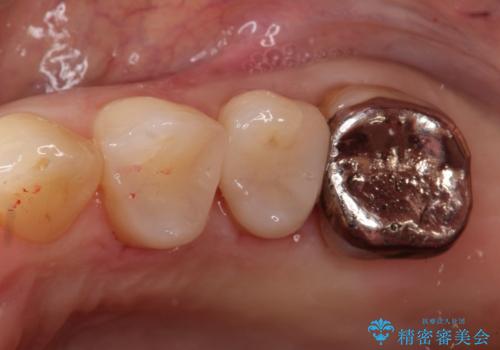

銀歯からセラミックへ。右上奥歯の精密根管治療と審美修復

担当医 河口智英